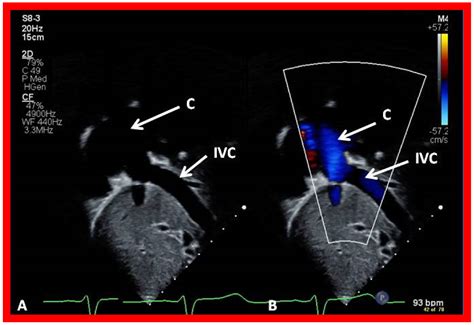

3. The Fontan Procedure: Typically performed between ages 2 and 5, this creates a final pathway for blood returning from the lower body to flow directly into the pulmonary arteries.

Living with Double Inlet Left Ventricle requires a lifelong partnership with a specialized medical team. As patients transition from childhood to adolescence and eventually adulthood, the focus shifts from surgical survival to optimizing long-term quality of life. This includes monitoring for potential complications such as arrhythmias, protein-losing enteropathy, or heart failure symptoms.

• double inlet lv fontan